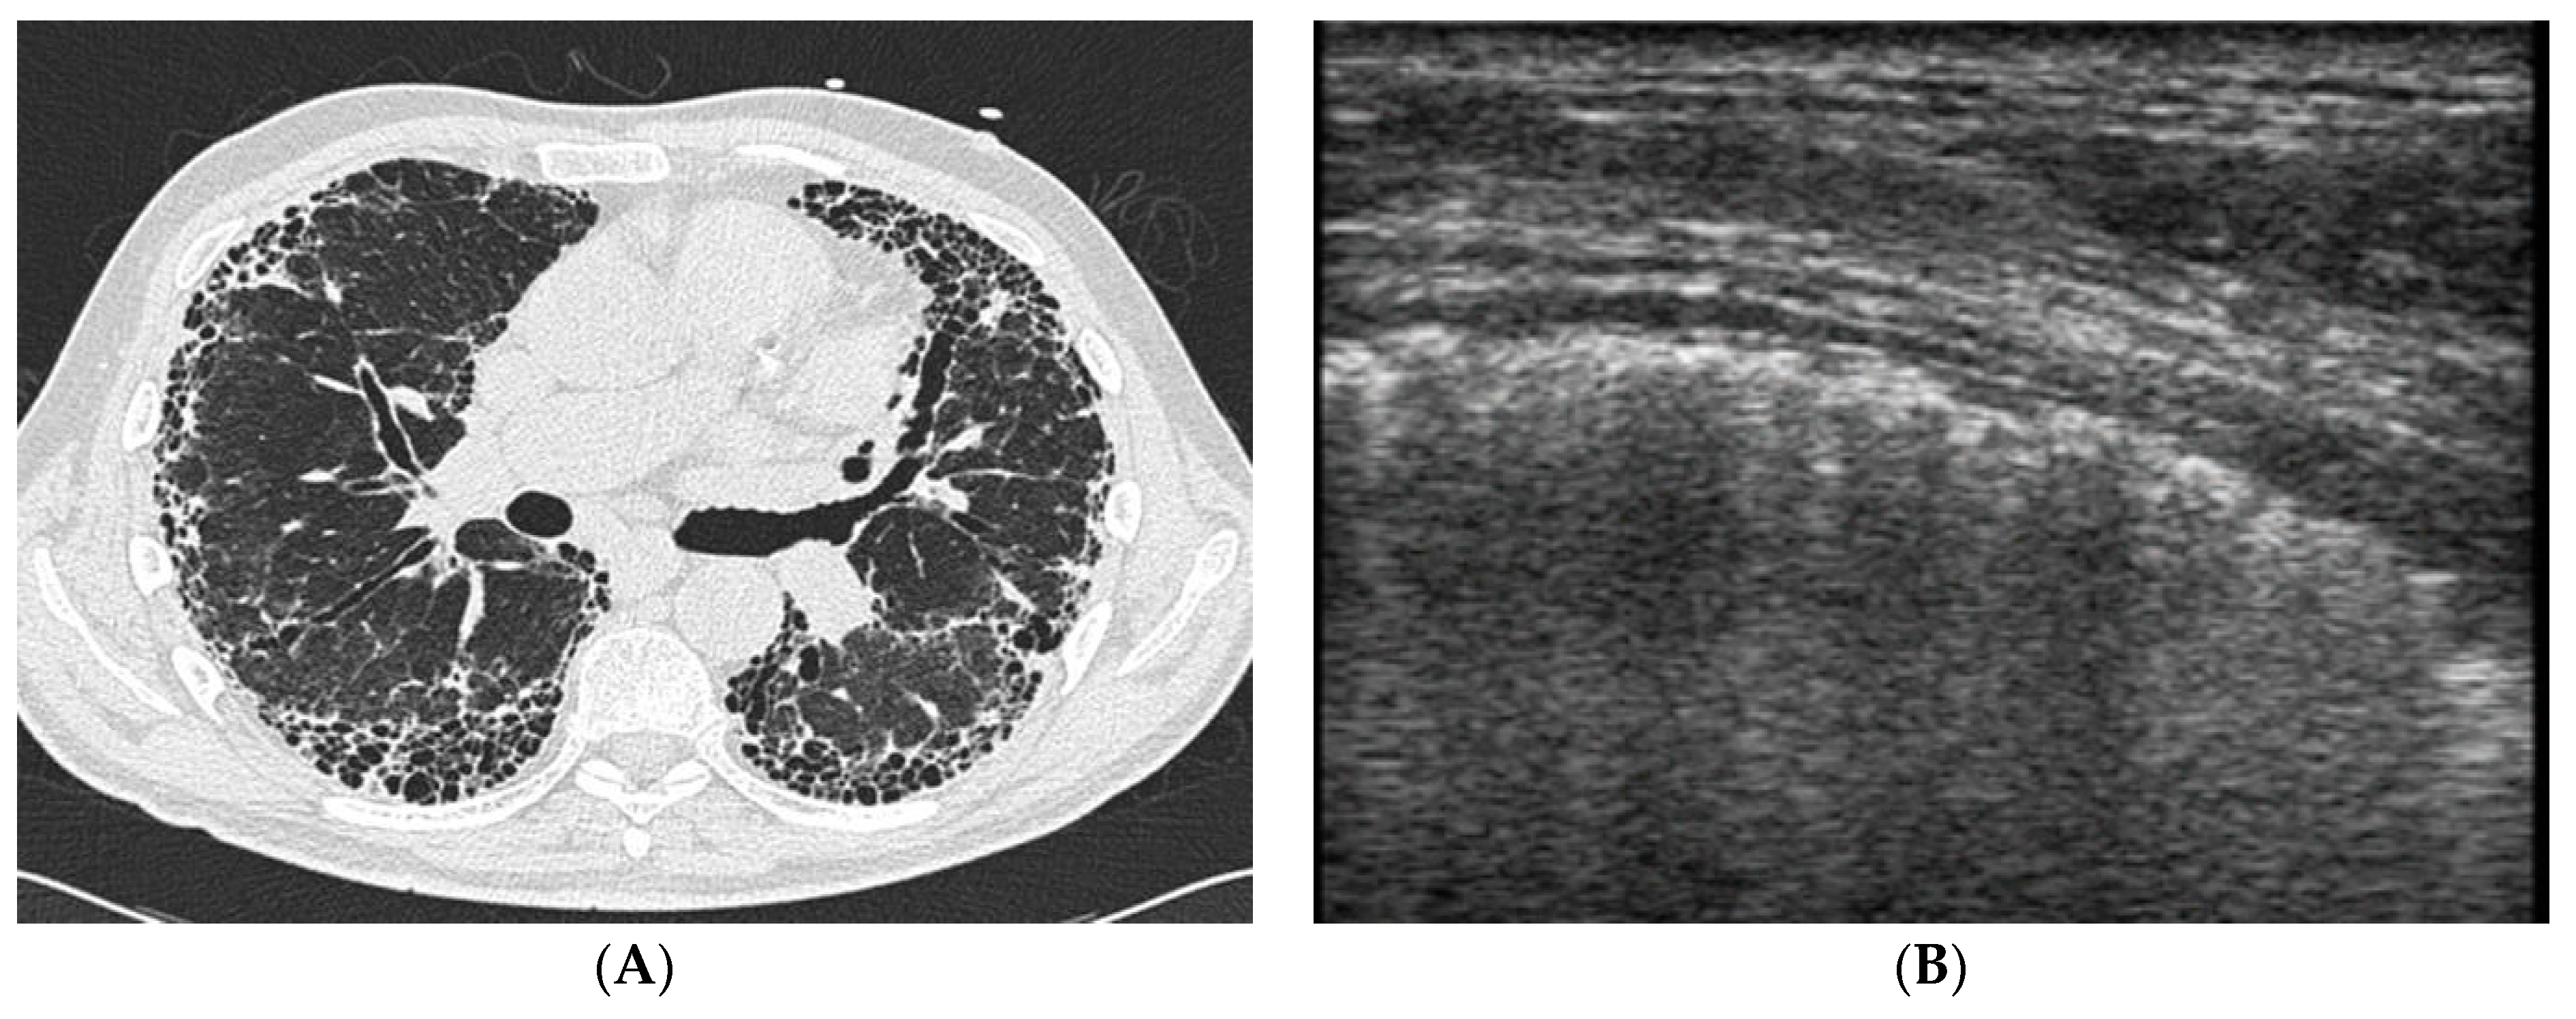

4.2. Does Lung Ultrasound (LUS) Have a Defined Role in pSS-ILD Screening and Follow-Up?

- Lichtenstein, D.A. Lung ultrasound in the critically ill. Ann. Intensive Care 2014, 4, 1–12. [Google Scholar] [CrossRef]

- Picano, E.; Frassi, F.; Agricola, E.; Gligorova, S.; Gargani, L.; Mottola, G. Ultrasound Lung Comets: A Clinically Useful Sign of Extravascular Lung Water. J. Am. Soc. Echocardiogr. 2006, 19, 356–363. [Google Scholar] [CrossRef]

- Yue Lee, F.C.; Jenssen, C.; Dietrich, C.F. A common misunderstanding in lung ultrasound: The comet tail artefact. Med. Ultrason. 2018, 20, 379–384. [Google Scholar] [CrossRef]

- Gutierrez, M.; Tardella, M.; Rodriguez, L.; Mendoza, J.; Clavijo-Cornejo, D.; García, A.; Bertolazzi, C. Ultrasound as a potential tool for the assessment of interstitial lung disease in rheumatic patients. Where are we now? La Radiol. Med. 2019, 124, 989–999. [Google Scholar] [CrossRef]

- Reissig, A.; Kroegel, C. Transthoracic sonography of diffuse parenchymal lung disease: The role of comet tail artifacts. J. Ultrasound. Med. 2003, 22, 173–180. [Google Scholar] [CrossRef]

- Gargani, L.; Doveri, M.; D’Errico, L.; Frassi, F.; Bazzichi, M.L.; Delle Sedie, A.; Scali, M.C.; Monti, S.; Mondillo, S.; Bombardieri, S.; et al. Ultrasound lung comets in systemic sclerosis: A chest sonography hallmark of pulmonary interstitial fibrosis. Rheumatology 2009, 48, 1382–1387. [Google Scholar] [CrossRef] [PubMed]

- Gigante, A.; Fanelli, F.R.; Lucci, S.; Barilaro, G.; Quarta, S.; Barbano, B.; Giovannetti, A.; Amoroso, A.; Rosato, E. Lung ultrasound in systemic sclerosis: Correlation with high-resolution computed tomography, pulmonary function tests and clinical variables of disease. Intern. Emerg. Med. 2016, 11, 213–217. [Google Scholar] [CrossRef] [PubMed]

- Barskova, T.; Gargani, L.; Guiducci, S.; Randone, S.B.; Bruni, C.; Carnesecchi, G.; Conforti, M.L.; Porta, F.; Pignone, A.; Caramella, D.; et al. Lung ultrasound for the screening of interstitial lung disease in very early systemic sclerosis. Ann. Rheum. Dis. 2013, 72, 390–395. [Google Scholar] [CrossRef] [PubMed]

- Gutierrez, M.; Salaffi, F.; Carotti, M.; Tardella, M.; Pineda, C.; Bertolazzi, C.; Bichisecchi, E.; Filippucci, E.; Grassi, W. Utility of a simplified ultrasound assessment to assess interstitial pulmonary fibrosis in connective tissue disorders—Preliminary results. Arthritis Res. Ther. 2011, 13, R134. [Google Scholar] [CrossRef]

- Tardella, M.; Gutierrez, M.; Salaffi, F.; Carotti, M.; Ariani, A.; Bertolazzi, C.; Filippucci, E.; Grassi, W. Ultrasound in the Assessment of Pulmonary Fibrosis in Connective Tissue Disorders: Correlation with High-Resolution Computed Tomography. J. Rheumatol. 2012, 39, 1641–1647. [Google Scholar] [CrossRef]

- Vasco, P.G.; Cardenal, G.D.L.; Garrido, I.M.; Pinilla, J.M.L.; Rodríguez, G.F.; Mateo, J.J.N.; Ruiz, D.C. Assessment of interstitial lung disease in Sjögren’s syndrome by lung ultrasound: A pilot study of correlation with high-resolution chest tomography. Intern. Emerg. Med. 2017, 12, 327–331. [Google Scholar] [CrossRef]

- Ferro, F.; Bulleri, A.; Elefante, E.; Tripoli, A.; Mosca, M.; Baldini, C. AB0510 Lung Ultrasound of Pleural Irregularities in Sub-clinical Primary Sjögren’s Syndrome-Lung Involvement: A Single Centre Experience. Ann. Rheum. Dis. 2019, 78 (Suppl. S2), 1718. [Google Scholar] [CrossRef]

- Ferro, F.; Sedie, A.D. The use of ultrasound for assessing interstitial lung involvement in connective tissue diseases. Ann. Rheum. Dis. 2018, 36 (Suppl. S114), 165–170. [Google Scholar]